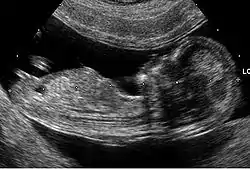

Ecografía genética

La ecografía genética o simplemente eco genético es un tipo de ultrasonido obstétrico que consiste en la valoración del feto para demostrar o descartar cualquier alteración anatómica o del estado de la salud del medio intrauterino reportando hallazgos o marcadores que pueden orientar en la identificación de fetos que tengan alteraciones cromosómicas.[1] La ecografía genética no tiene una precisión absoluta, de manera que una ecografía normal no garantiza que el bebé sea normal y hallazgos considerados anormales por un ecografista no garantiza que el bebé no sea normal.[1]

El eco genético suele realizarse en el segundo trimestre con el fin de detectar anomalías, incluyendo defectos estructurales así como también defectos no estructurales, que son los llamados marcadores ecográficos.[6] Los más comunes observados en las ecografías del segundo trimestre, son el engrosamiento del pliegue nucal, el intestino hiperecogénico, el acortamiento de los huesos largos (principalmente el húmero y fémur), la pielectasia renal, los focos ecogénicos intracardíacos y los quistes de los plexos coroideos.[7] Muchos de estos hallazgos, sin embargo, pueden conseguirse de manera aislada en fetos euploides, y aparecer sólo de manera temporal, por tanto la interpretación de los mismos debe ser cuidadosa.